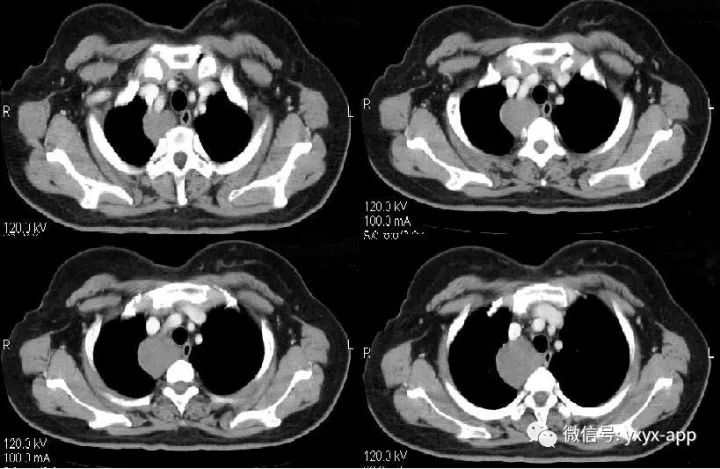

肚肚丫头:右上后纵隔、气管右旁、脊柱前方可见类圆形软组织密度影,与气管及食管均关系,增强后无明显强化,考虑囊肿,起源待定。

支气管囊肿是一种较少见的先天性疾病,系由胚胎发育障碍引起,分纵隔型和肺内型。支气管囊肿的发生部位:1. 纵隔型:纵隔型支气管囊肿大部分位于纵隔。典型发病部位为中纵隔、气管或主支气管旁、气管隆突下,右侧多见。2. 肺内型:肺内型支气管囊肿的发病部位一般认为下肺比上肺多见,左肺比下肺多见,有时位于肺门,与支气管走形一致。

CT表现:纵隔旁支气管囊肿其典型形态为圆形、类圆形、水滴形、长条形,偶为分叶状,边缘均清楚锐利,内部密度多较均匀。肺内型表现为单发的气囊肿、液囊肿、液-气囊肿或多发囊肿,边界清楚,囊壁薄而均匀,可合并肺发育不良、肺隔离症、肺气肿及胸廓塌陷等其他肺内畸形。CT值差异较大,多为20~30HU,最高可达80HU,反映囊肿内容物的不同成分,囊肿不与支气管相通时形成含液囊肿,与支气管相通时囊液会全部或部分排出,形成含气囊肿或含气液囊肿。如有感染、出血或囊壁受到刺激可以使壁增厚、毛糙,囊液也可以变得更粘稠,或者分泌的黏液含有高蛋白成分、钙乳样物质等,均可导致囊肿内密度增高,从而CT表现为软组织密度、实性肿块。CT增强扫描有助于判断囊壁及囊腔内容物的强化程度,提示诊断。支气管囊肿的强化特征为囊内容物无强化,囊壁可强化,是由于囊壁含有平滑肌成分,如合并感染、肉芽组织增生,囊壁可增厚、强化。